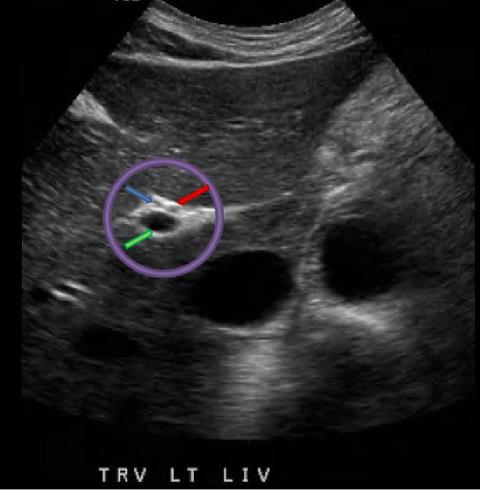

What structure is indicated by the blue arrow?

Right portal vein

What structure is indicated by the purple circle?

Portal triad

What structure is indicated by the green arrow?

Main portal vein